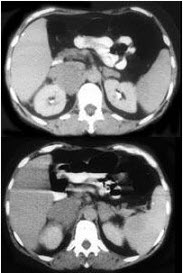

男,65岁,腋下触及肿大包块,全身浅表淋巴结肿大,结合所示图像,最可能的诊断是()

A . 双侧肾上腺腺瘤

B . 双侧肾上腺增生

C . 双侧肾上腺淋巴瘤

D . 双侧肾上腺转移癌

E . 肾上腺癌

男,65岁,腋下触及肿大包块,全身浅表淋巴结肿大,结合所示图像,最可能的诊断是(

[单选题]男,65岁,腋下触及肿大包块,全身浅表淋巴结肿大,结合所示图像,最可能的诊断是()A .双侧肾上腺腺瘤B .双侧肾上腺增生C .双侧肾上腺淋巴瘤D .双侧肾上腺转移癌E .肾上腺癌